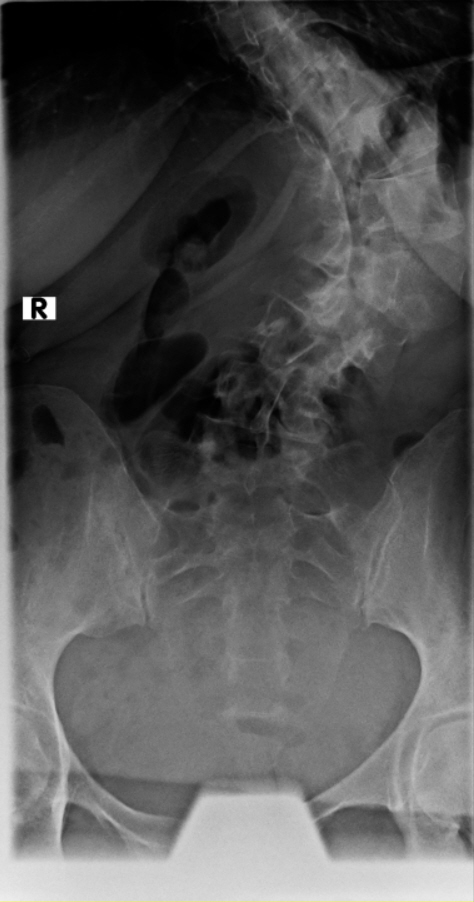

Thorakolumbalskoliose mit aktuellen COBB-Winkeln von 80 und 60 Grad...wenig Schmerzen und daher meistens glücklich

Viele kennen sich aus, daher möchte ich euch meine aktuellen Röntgenbilder nicht vorenthalten und hänge sie unten an.

Ich war beim MVZ Gersthofen, dort wurden die Röntgenbilder gemacht…die massive Verschlechterung war sehr offensichtlich

Dort wurden die Winkel gemessen, unten 80 Grad und oben 60 Grad…eine Verschlechterung von über 2 Grad pro Jahr, wenn man es auf die ganze Zeit berechnet